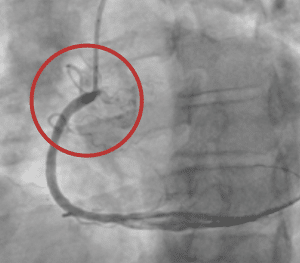

Large Thrombus Burden, Pre Aspiration